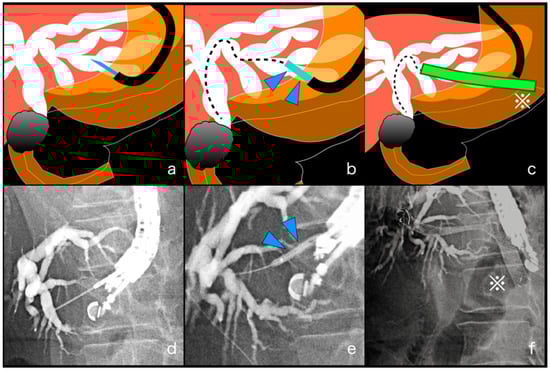

2.2. EUS-HGS and EUS-HGAS